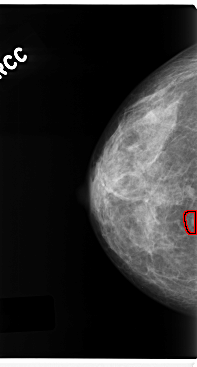

C_0212_1.RIGHT_CC

FILE: C_0212_1.RIGHT_CC.OVERLAY

TOTAL_ABNORMALITIES 1

ABNORMALITY 1

LESION_TYPE MASS SHAPE ROUND MARGINS CIRCUMSCRIBED

ASSESSMENT 4

SUBTLETY 5

PATHOLOGY MALIGNANT

TOTAL_OUTLINES 1

BOUNDARY